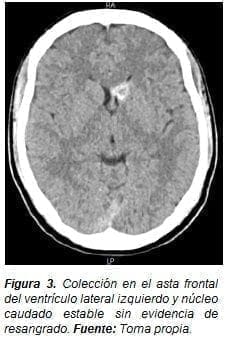

Debido a la evolución satisfactoria de la paciente, se decide su traslado a la Unidad de Cuidados Intermedios (UCINT). En esta unidad, se sigue notando la evolución favorable de la paciente por lo que se solicita la práctica de un TAC cerebral simple para revalorar el área de sangrado. En los resultados, se evidencia la resolución del edema cerebral y se observa la colección en el asta frontal del ventrículo lateral izquierdo como estable, sin registro de resangrado (Figura 3). En consecuencia, se decide dejar a la paciente en observación durante 24 horas antes de decidir su salida. Asimismo, se solicita la valoración por parte de Neurología Clínica, en la cual se determinó que había: esfera mental normal, buena capacidad de abstracción, marcha normal, y ausencia de movimientos involuntarios. La especialidad estuvo de acuerdo con el egreso de la paciente. Finalmente, cinco días después de su ingreso, por la ausencia de complicaciones posteriores al sangrado intracraneal, gracias a la evolución satisfactoria y a la excelente respuesta al examen neurológico.